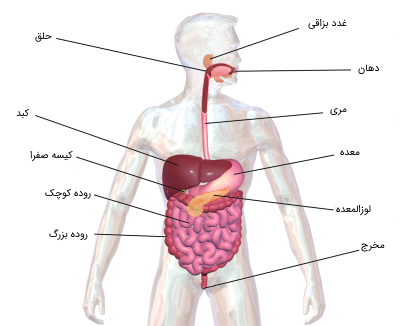

عکس داخل شکم انسان. در این همان طور که مشخص است شکم حالت بیضی شکل پیداکرده و این بیضی که کناره های شکم کشیده شده است. تعداد سلول های بدن انسان حدود ۳۷ ۲ تریلیون تخمین زده شده اند. Abdomen که در زبان عامه به غلط به آن دل نیز می گویند در آناتومی به قسمتی از تنه گفته می شود که مابین دیافراگم از بالا و سطح فوقانی لگن خاصره از پایین قرار دارد. ربات دیدنی ربات انساننمای چینی به صورت یک دختر جوان ساخته شده و جیا جیا نامگذاری شده است این ربات طوری برنامهریزی شده که میتواند صحبت کند و احساسات خود را از طریق تغییرات در چهره حالات.

شکل دوم شکم مادری را نشان می دهد که جنین دختر دارد. وحشت مادر از عکس سونوگرافی جنین داخل شکمش عکس. تصاویر جالب از داخل مغز و نخاع انسان آخرین نیوز. بدن انسان کل ساختار انسان است که سر گردن تنه سینه و شکم دو بازو و دست ها و دو ساق پا و پاها را شامل می شود.